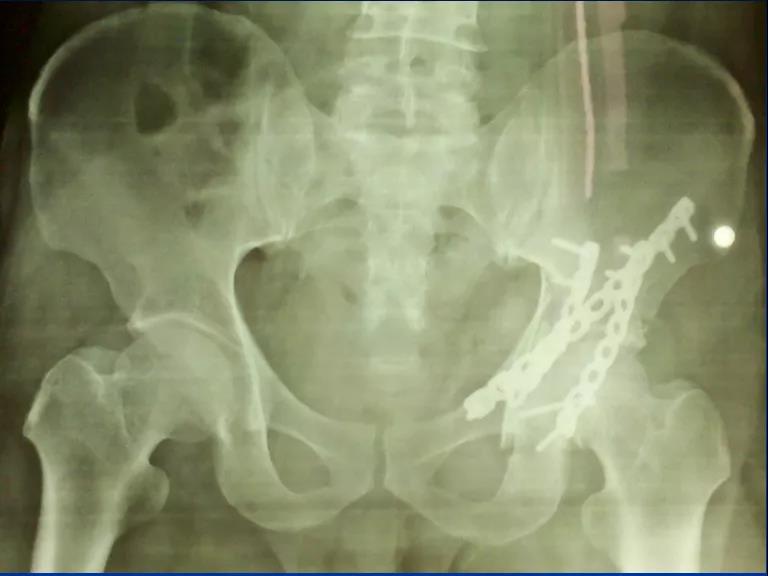

髋关节融合术的温哥华术式!